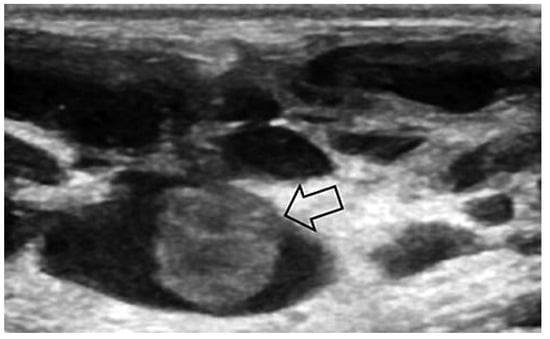

Case report A 22-year-old male experienced a presyncopal spell while studying for a university examination [...]